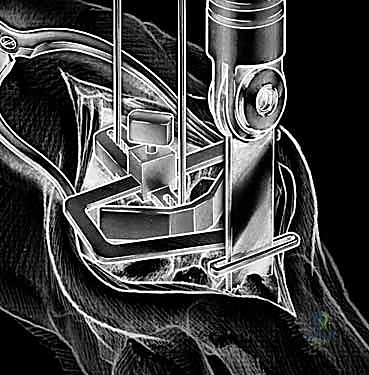

With the wrist held in neutral, the radius is scored through the cutting slot in the guide to provide a reference for the distal radial resection. The thumbscrew on the carpal resection guide is loosened to allow insertion of the radial resection guide boom. Following radial resection, the scaphoid, capitate head, hamate edge, and triquetrum are resected at a precise 90-degree angle to the axis of the forearm jig. The trial carpal plate is provisionally determined by the curvature and width of the remaining proximal carpal surface; it must lie flush with the hamate and proximal capitate surfaces. Unlike older designs, it is not always necessary to attempt fusion of the distal pole of the scaphoid to the surrounding carpus. The Maestro Wrist has a provision to replace the entire scaphoid using a carpal plate incorporating a modular radial augment, of which three separate sizes are available.

Following capitate reaming, the chosen carpal plate and stem are assembled and inserted into the capitate and seated onto the resected carpal surface. The carpal plate is anchored to the carpus with a radial screw that optimally does not penetrate the second metacarpal, and a second screw placed ulnarly into the hamate. This construct ensures stable distal fixation while avoiding the deleterious lever arm of a long metacarpal stem. Trial reductions are performed to assess stability, range of motion, and impingement. Once kinematics are confirmed, the definitive ultra-high-molecular-weight polyethylene (UHMWPE) body—which is direct compression molded onto a cobalt chrome alloy radial body—is impacted. The capsule and extensor retinaculum are meticulously repaired to prevent extensor tendon bowstringing and provide a robust soft tissue envelope over the implant.